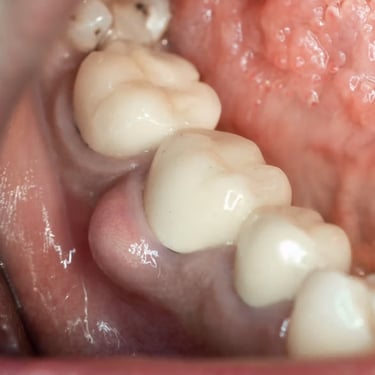

Quiste Periapical

Un quiste periapical es una cavidad llena de líquido en la punta de la raíz del diente, generalmente resultado de una infección crónica.

Los pacientes pueden notar una hinchazón sin dolor en la encía.

El tratamiento incluye el tratamiento de conducto y, a veces, la extirpación quirúrgica del quiste. Si no se trata, el quiste puede crecer y causar complicaciones.